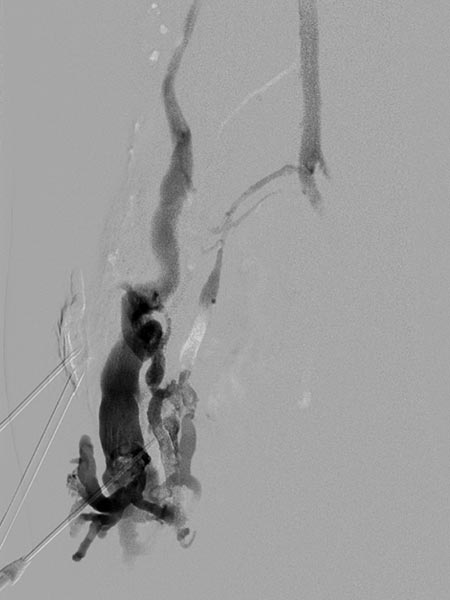

Digital subtraction angiography after direct puncture of the venous malformation during sclerotherapy. In addition to the lesion, direct communicating veins with the deep conducting vein system are visible. These were occluded with viscous alcohol gel by direct puncture.

X-ray fluoroscopy after direct puncture of the venous malformation during sclerotherapy. As a result of closure of the communicating veins to the deep venous system, the VM is now isolated and can be sclerosed. After injection of contrast, no outflow of the contrast medium into the deep veins.